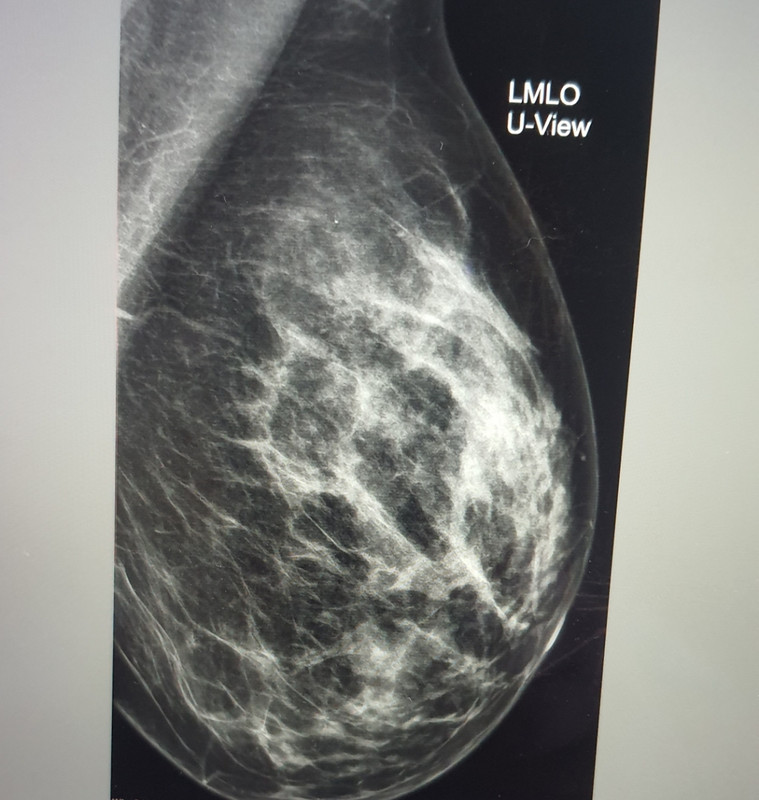

però io vedo che in molti casi di seni densi viene prescritta semplice eco. Poi il radiologo mi spavento' con le sue parole "signora, io non ho detto che non ha nulla, stanno tutti qui (i noduli), io vi sto dicendo di fare rm di corsa" .. non ti dico quel momento come fu; per contro, il senologo mi tranquillizza. Ora sto nella fase del limbo/paura. In realtà per sfizio vorrei sapere il parere del prof pure sul seno che il radiologo mi disse essere molto denso (disse un D pieno) ma a me sembra più un C.. giusto per curiosità (per smaniare un po', lo so che non serve a nulla) a voi come sembra ? A me un D sembra piu denso del mio. Metto foto del seno sinistro (dove sotto ho retrazione cutanea purtroppo) :